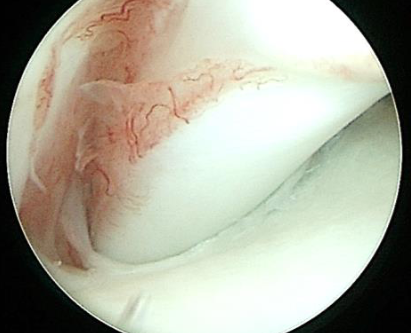

Image of a healthy dog biceps tendon.

Visual assessment identifies an injured canine biceps tendon, consistent with a partial avulsion. Concomitant synovitis is noted, indicative of significant joint inflammation.